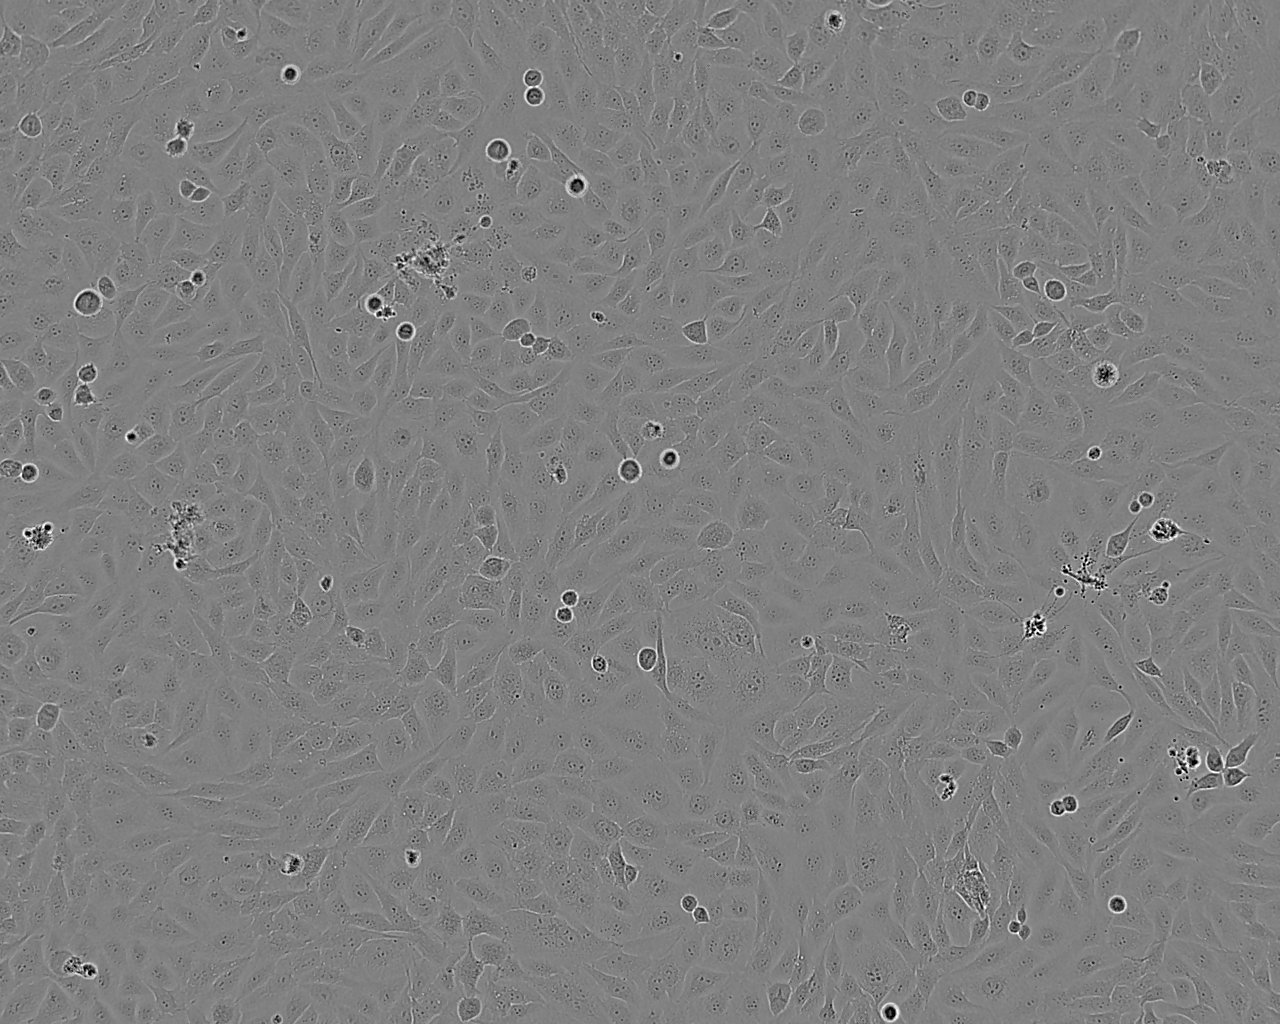

细胞形态:上皮细胞样

细胞生长:贴壁

细胞背景资料:转移性小叶乳腺癌;胸腔积液转移;女性

细胞生长特性:贴壁